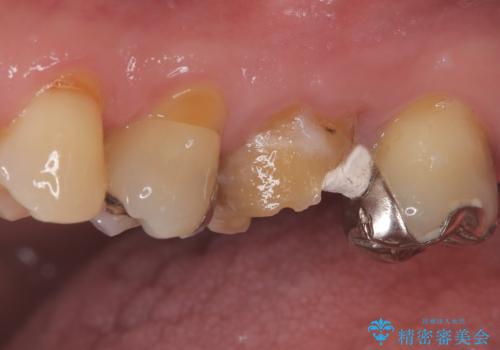

他院で治らなかった根管治療を精密治療で改善|MB2を発見し再治療

- 患者様は、他院で根管治療を受けていたが、なかなか治らず、より精密な治療を希望して当院を受診されました。マイクロスコープを使用して詳しく診断したところ、上顎第一大臼歯(6番)のMB2(第二頬側根管)の見落としが判明。このままでは感染が残り、再発のリスクが高い状態であるため、当院で精密根管治療を行う方針としました。

マイクロスコープを使用してMB2を確認し、感染源を徹底的に除去。その後、根管内を清掃・消毒し、高品質な充填材で密閉しました。従来の根管治療では見落とされがちなMB2の発見により、治療の精度が大幅に向上し、炎症の改善が期待できる状態となりました。患者様からは「治療後の違和感がなくなり、しっかり噛めるようになった」と喜びの声をいただきました。